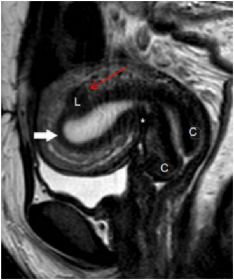

病例:子宫肌瘤,女性,42岁,痛经10余年。磁共振盆腔成像清晰显示子宫肌瘤(箭头示L)。

对于妊娠的妇女,大孔径磁共振在欧美已经为首选检查,能够令患者在髋关节屈曲的舒适体位上实现精准的胎儿成像,保证不会对孕妇的心肺功能带来压力。此外,妇科疾病或男性生殖系统疾病通常导致患者盆腔疼痛,扫描时髋关节无法长时间伸展,大孔径的超大空间允许患者在扫描过程中始终保持髋关节屈曲的状态,在最大程度上提升了患者的舒适感和配合度。